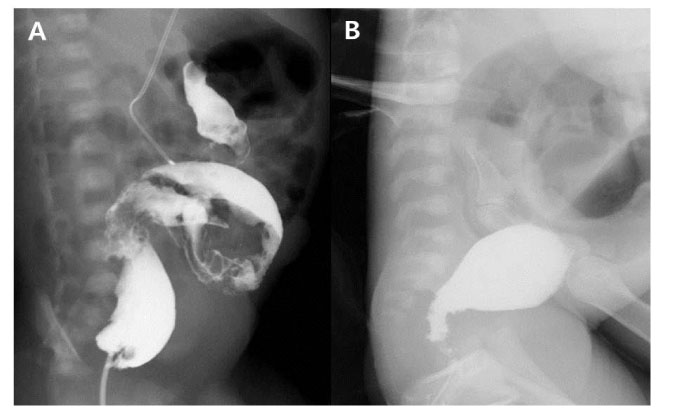

A case who required repeated contrast enema (CE). Transition zone was not observed in the first CE (A), but clear transition zone was identified in the second CE (B).

Fig. 1 A case who required repeated contrast enema (CE). Transition zone was not observed in the first CE (A), but clear transition zone was identified in the second CE (B).